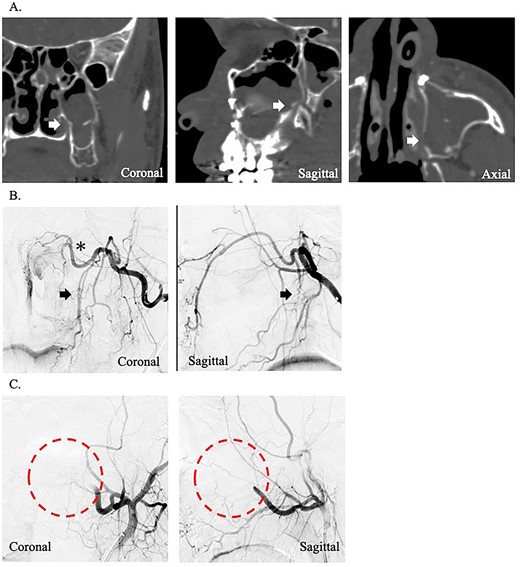

A 24-year-old man presented to our department with massive epistaxis from the left nose. The patient underwent Le Fort I maxillary osteotomy and sagittal split ramus osteotomy for jaw deformity 10 days earlier by the dentist at another hospital and had repeated epistaxis episodes after hospital discharge. After the patient came to our hospital, the left nasal cavity was examined endoscopically; however, the hemorrhage had stopped, and no definite bleeding points were identified. Contrast-enhanced computed tomography of the paranasal area revealed that the maxilla and pterygoid fragment were cut and separated. In addition, a cut of the bone was found around the descending palatine artery, as in case 1 (Fig. 2A). The preoperative hemoglobin concentration was 14.2 g/dL, and the hematocrit was 40.0%. After hemorrhage, the hemoglobin concentration (11.3 g/dL) and hematocrit (32.4%) decreased. After hospitalization, massive hemorrhage recurred, and hemostasis was impossible by endoscopy. Therefore, angiographic embolization by a radiologist was selected. The angiography revealed vascular injury to the left descending palatine artery, and embolization was performed by gelatin sponges (Fig. 2B and C). As in case 1, hemostasis was sufficiently complete; however, after angiographic embolization, the hemoglobin concentration and hematocrit severely decreased to 9.3 g/dL and 27.5%, respectively.

(A) Postoperative coronal, sagittal, and axial computed tomography images, which show the separated bone parts of the left maxilla (arrow). (B) Coronal and sagittal selective angiographic images from the left internal maxillary artery. The arrows indicate the suspected region of injury to the left descending palatine artery. The asterisk indicated the left sphenopalatine artery. (C) After embolization and coronal and sagittal selective angiographic images. The circle indicated the disappearance of the vascular flow area.